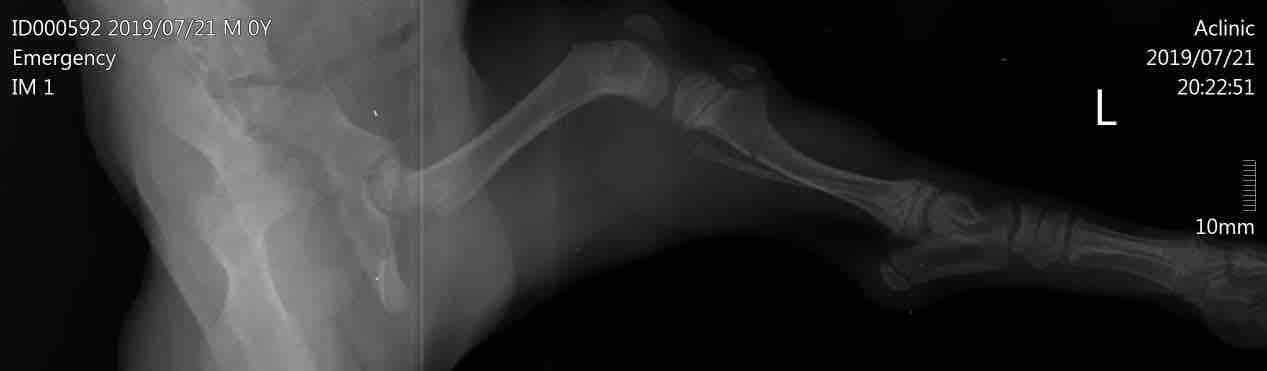

My dog put a supporting wrap on his leg 3 days ago but i cant make him stop move he wants to move in the home and when i put him in box and close it he start cry . That will lose him healing?! Or just slow his recovery? And have any solutions plz

This question includes photos that may contain sensitive content. Click to view.

With a broken bone, Biko should not be walking around at all. You need to keep him in a kennel to allow the leg the best chance to heal. He should also be in a splint, not a supportive wrap. He may need sedatives. I recommend to call the veterinarian and tell them what is happening. They can provide a splint as well as sedation for Biko. It will take 6 to 8 weeks for the bone to fully heal. I hope this helps and please feel free to post any additional questions.